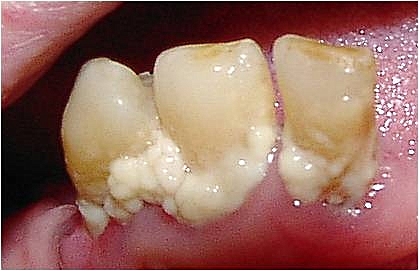

치태는 치아 표면에 형성되는 세균 덩어리로, 펠리클이라는 타액층에 세균이 부착되어 생물막을 이루며 형성된다. 치태는 다양한 세균, 주로 뮤탄스 연쇄상구균과 혐기성 세균으로 구성되며, 치은연상 치태와 치은연하 치태로 나뉜다. 치태는 치아 우식증과 치주 질환의 주요 원인이며, 심혈관 질환, 호흡기 질환 등 전신 질환과도 관련될 수 있다. 치태는 칫솔질, 치실 사용 등의 구강 청결 관리를 통해 관리하며, 치태 착색제를 사용하여 검출할 수 있다.

치태의 유기질 성분은 약 70%가 미생물이며, 대부분은 세균(구강 상재균)과 그 대사 산물이다. 구강 내 청결 상태에 따라 세균이 변화하여 치주 질환이나 충치 등 다양한 질환의 원인이 되며, 구취 등을 유발한다. 치태 염색제를 통해 구강 내 치태의 분포를 쉽게 조사할 수 있다. 일상적인 구강 청결 관리(칫솔이나 치실 등)를 통해 대부분 제거할 수 있지만, 모두 제거하는 것은 어렵다. 제거하기 어려운 부위 (특히 치아의 씹는 면, 치아와 치아 사이의 면, 치아와 잇몸 사이)는 치과 병원에서 PMTC를 정기적으로 받는 것이 바람직하다.

치태를 구성하는 주된 미생물은 ''뮤탄스 연쇄상구균(Streptococcus mutans)''과 푸소박테리움, 방선균 등의 혐기성 세균이다.[1] 이들은 구강 내 위치에 따라 구성이 달라진다.[1] ''뮤탄스 연쇄상구균''은 글루칸수크라제 효소를 이용해 자당을 끈적한 세포외 덱스트란 기반 다당류로 만들어 세균이 뭉쳐 치태를 형성하게 한다.[9]치태 형성 초기에는 그람 양성 구균이 많지만, 시간이 지나면서(3~4일) 실과 방추형균이 늘어나고, 4~9일 후에는 간균, 사상성 형태 등 더 복잡한 세균총이 형성된다. 7~14일이 지나면 ''비브리오''속, 스피로헤타류, 그람 음성 세균이 많아진다.[10]

치아 우식증(충치)은 주로 뮤탄스 연쇄상구균에 의해 발생하는 감염성 질환으로, 치아의 에나멜이 산에 의해 부식되고, 더 나아가 내부 상아질까지 파괴될 수 있다.[1] 치태 내 세균 군집은 주로 산을 생성하고 산에 강한 종(예: 뮤탄스 연쇄상구균, 유산균)으로 구성되며, 비슷한 특성을 가진 다른 종도 관련될 수 있다.[31]

치태 내 세균은 음식물의 당질을 대사하여 산을 생성한다. 이 산은 치아 표면을 탈회시켜 충치를 유발한다.[1] 음식 섭취 후 잠시 동안 치태의 pH (수소 이온 지수)는 치아 탈회의 임계 pH (일반적으로 5.5 전후) 이하로 떨어진다. 이는 치태를 구성하는 충치 원인균이 음식의 당질을 대사하여 산으로 바꾸기 때문이다.